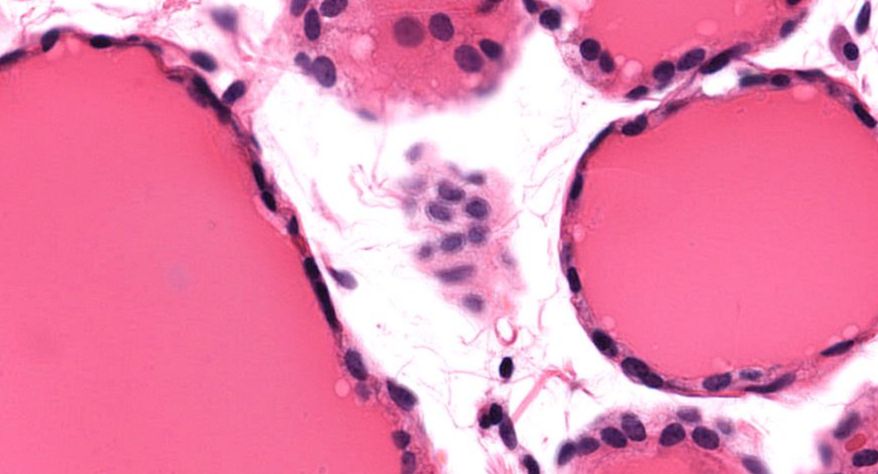

甲状腺

3.滤泡上皮细胞

4.胶质

5.滤泡旁细胞1